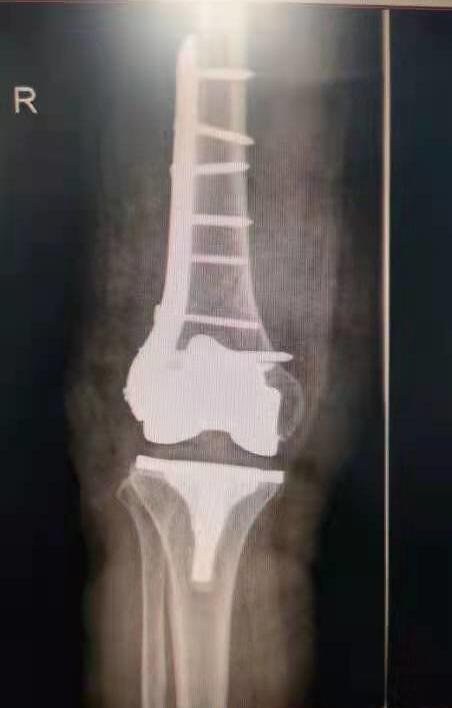

手术前照片

手术后照片